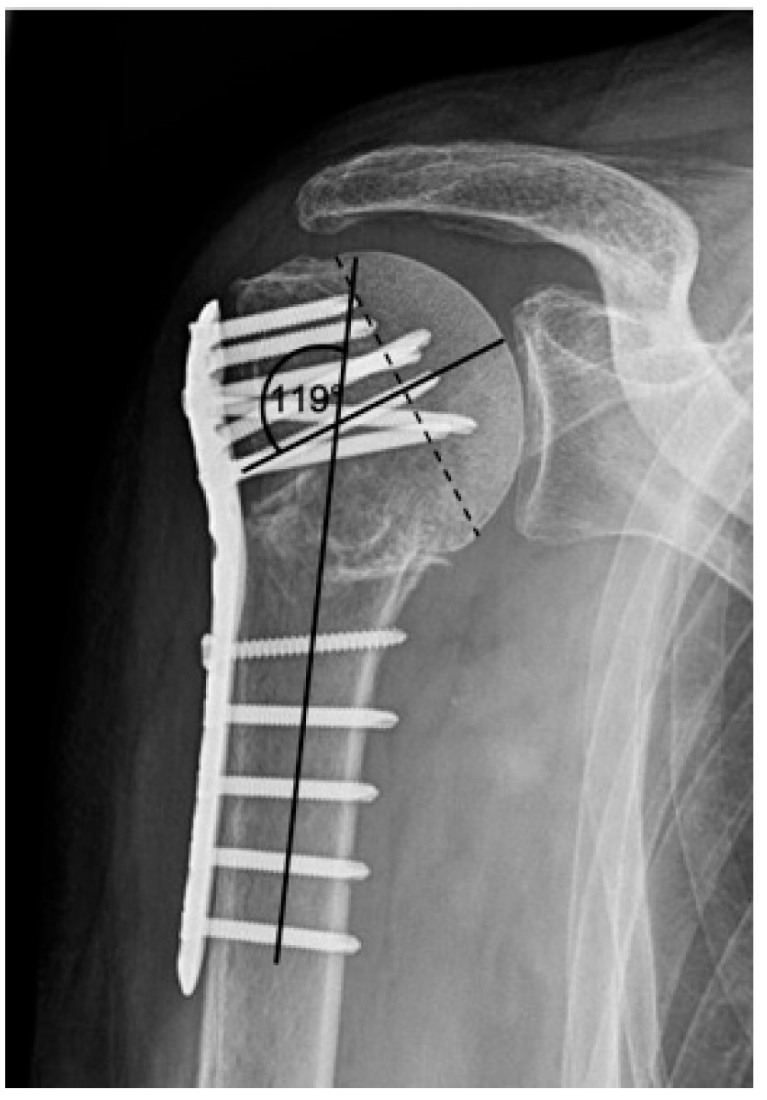

| 2c | ![]() | Type 2c is defined by a severe varus displacement (>20°) of the humeral head, which is associated with a screw cutout at the humeral head in parallel to Type 2a. In contrast to Type 2a, this varus displacement is characterized by an unstable osteosynthesis situation and progression. |